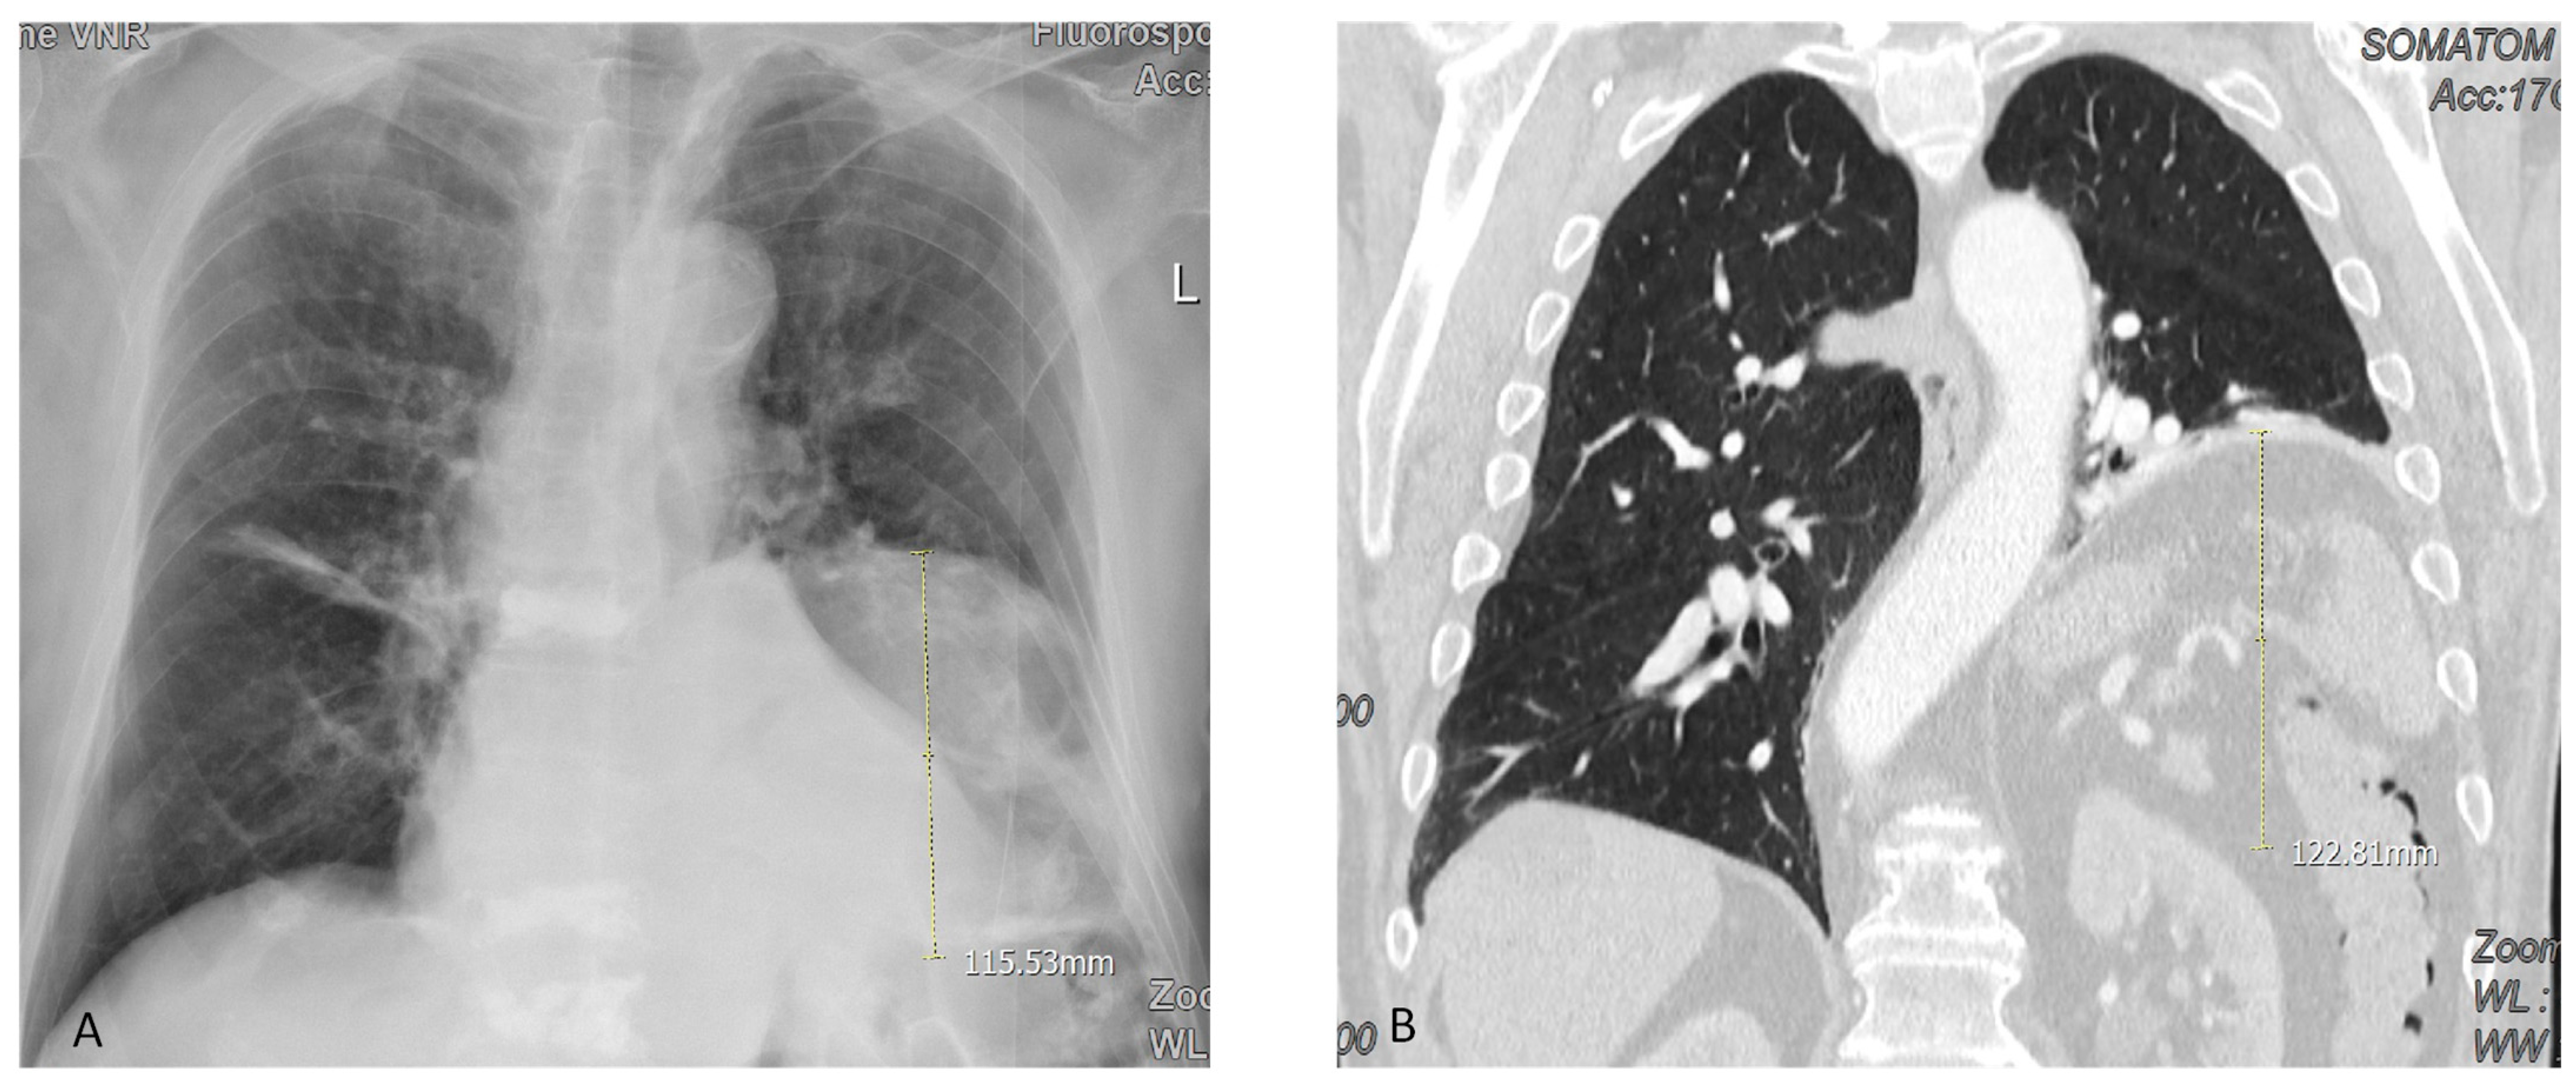

| Height of diaphragm om the X-ray (cm) | 8 ± 4 | 0.018 |